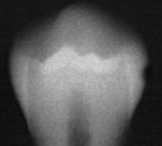

classify this according to radiographic presentation of the ADA

E1

classify this lesion according to the ADA and ICDAS/ICCMS systems

caries within the outer half of the enamel: RA1, E1